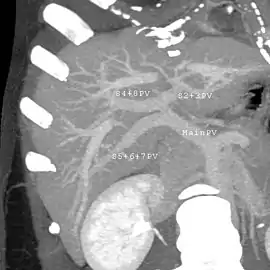

With the recent advances of noninvasive imaging, living liver donors usually have to undergo imaging examinations for liver anatomy to decide if the anatomy is feasible for donation. The evaluation is usually performed by multidetector row computed tomography (MDCT) and magnetic resonance imaging (MRI). MDCT is good in vascular anatomy and volumetry. MRI is used for biliary tree anatomy. Donors with very unusual vascular anatomy, which makes them unsuitable for donation, could be screened out to avoid unnecessary operations.

MDCT image. Portal venous anatomy contraindicated for liver donation